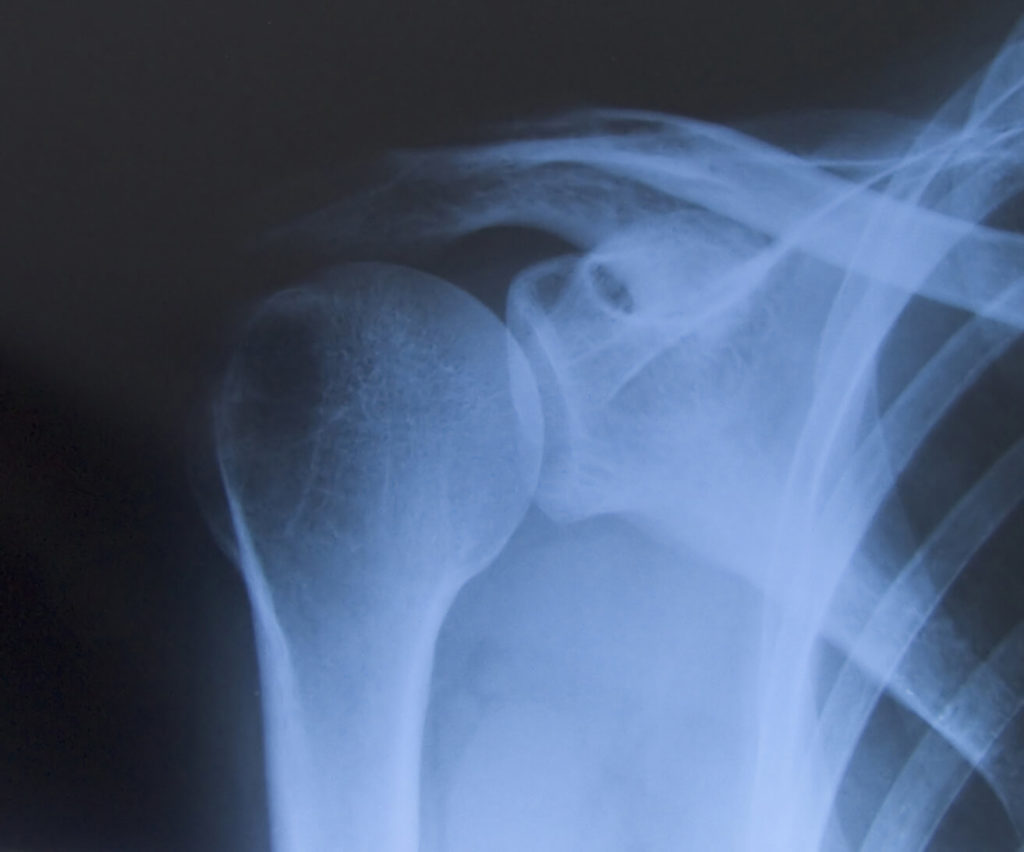

Op een thoraxfoto is zichtbaar of er granulomen in de longen aanwezig zijn. Ook de mate van ontsteking van de longen is goed te zien als een witte sluier over de longen. De beenderen in het longgebied kunnen op de thoraxfoto beoordeeld worden, zoals de ribben, het borstbeen of het schoudergewricht. Dit kan van belang zijn bij reumatische afwijkingen als gevolg van de vasculitis. Soms worden daarom ook röntgenfoto’s gemaakt van andere lichaamsdelen, zoals armen en benen of de gewrichten.